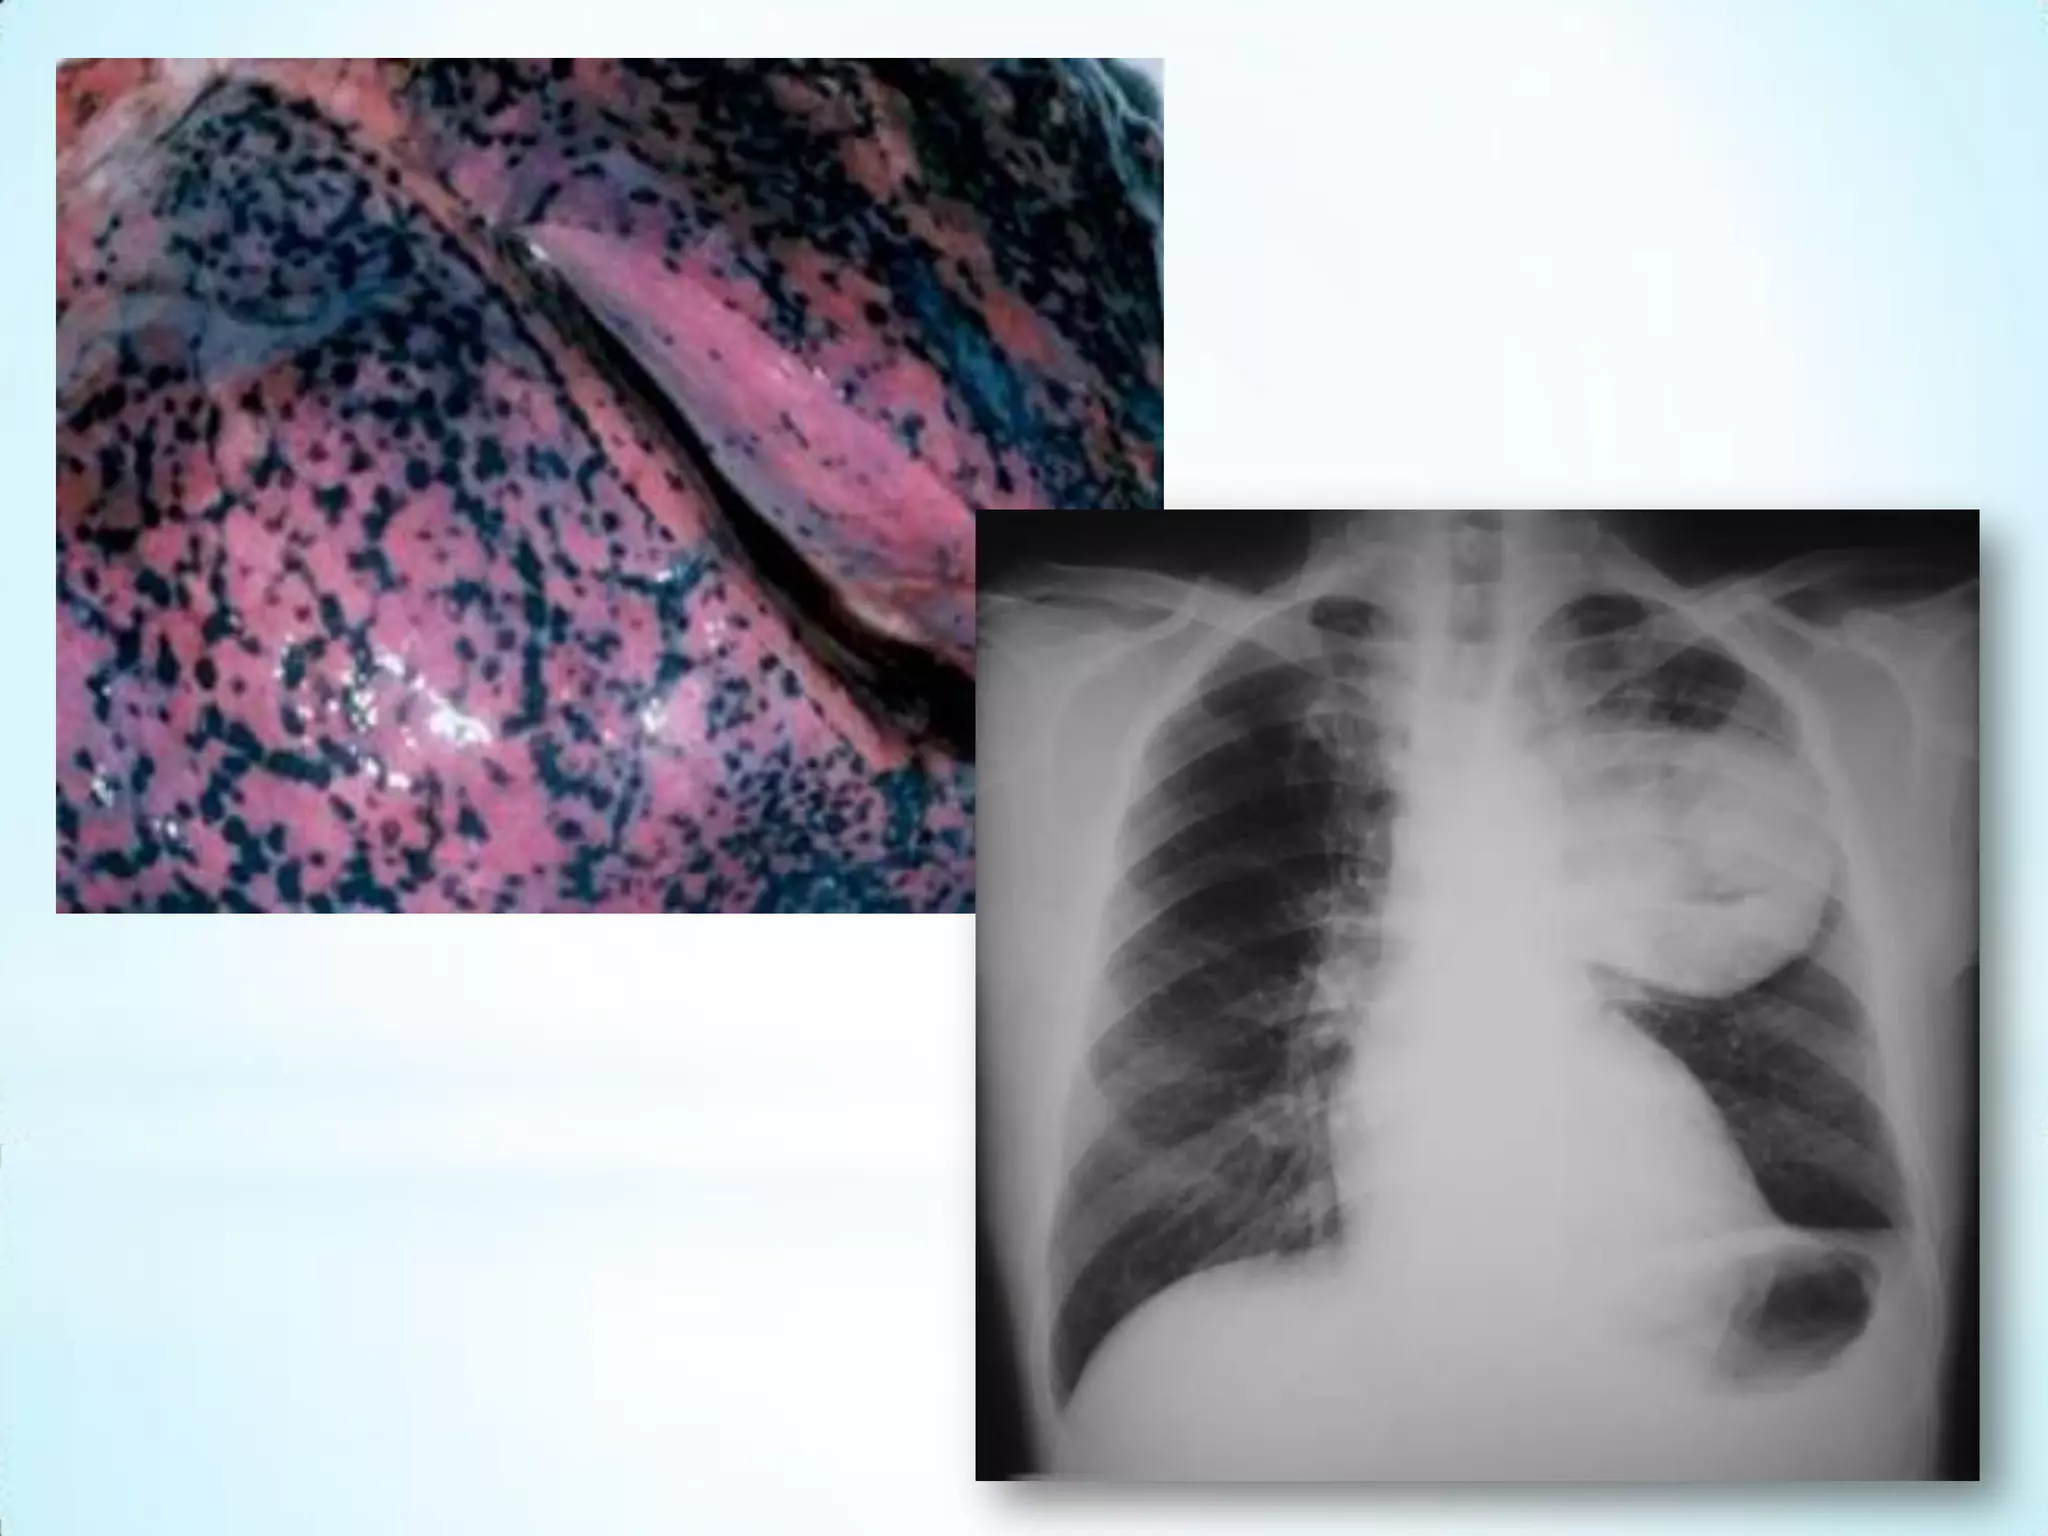

Câncer do Pulmão

O câncer de pulmão é um dos tumores malignos mais comuns, sendo

que sua incidência no mundo todo vem aumentando 2% a cada ano. A

mortalidade por esse tipo de neoplasia é muito elevada e o prognóstico

está relacionado à fase em que é diagnosticado.

O principal fator de risco para o aparecimento dessa neoplasia é o

tabagismo. Atualmente, este último corresponde a 90% dos casos desse

tumor. É mais comumente observado em homens do que em mulheres;

todavia, o número de casos em mulheres está aumentando, enquanto

que o número de casos em homens está diminuindo.

Esta neoplasia também pode ser causada por certos produtos

químicos, como:

arsênico, berílio, asbesto, radônio, níquel, cromo, cádmio e cloreto de

vinila, especialmente observados em ambiente ocupacional. Outros

fatores relacionados ao surgimento desse tumor são os

dietéticos, genéticos, histórico da DPOC e histórico de câncer de pulmão

na família.

Câncer do Pulmão Ocâncer de pulmão é um dos tumores malignos mais comuns, sendo que sua incidência no mundo todo vem aumentando 2% a cada ano. A mortalidade por esse tipo de neoplasia é muito elevada e o prognóstico está relacionado à fase em que é diagnosticado. O principal fator de risco para o aparecimento dessa neoplasia é o tabagismo. Atualmente, este último corresponde a 90% dos casos desse tumor. É mais comumente observado em homens do que em mulheres; todavia, o número de casos em mulheres está aumentando, enquanto que o número de casos em homens está diminuindo. Esta neoplasia também pode ser causada por certos produtos químicos, como: arsênico, berílio, asbesto, radônio, níquel, cromo, cádmio e cloreto de vinila, especialmente observados em ambiente ocupacional. Outros fatores relacionados ao surgimento desse tumor são os dietéticos, genéticos, histórico da DPOC e histórico de câncer de pulmão na família.